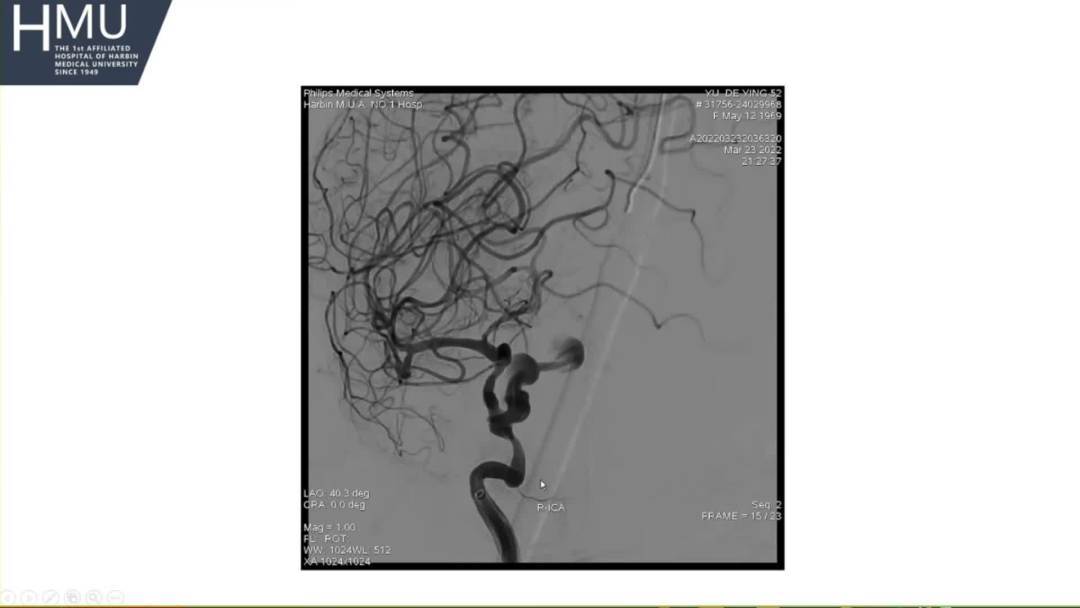

21:00覆膜支架置入术

海绵窦段动脉瘤如何导致蛛网膜下腔出血?

●大动脉瘤累及突破海绵窦硬膜